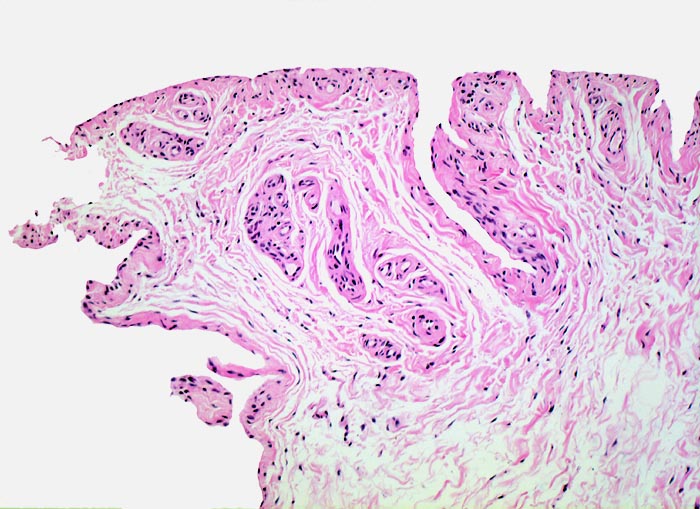

Normalbefund

Morphologische Merkmale:

• Synovialis mit verplumpten Zotten.

• Stark proliferierte mehrreihige synoviale Deckzellschicht.